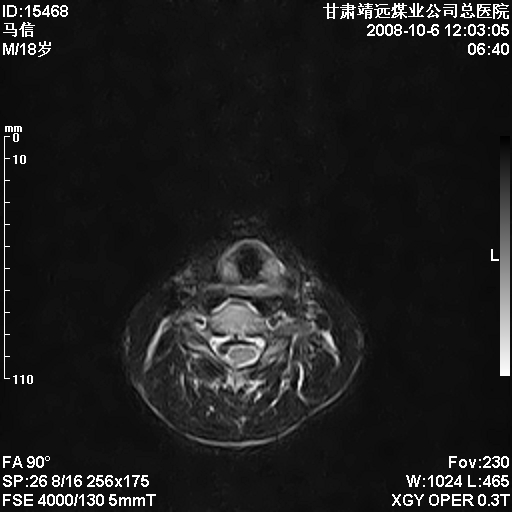

标题: MRI1827:颈椎内异常信号,是不是占位。

患者18岁,学生,在玩耍中受伤来检查,患者喜欢打篮球。颈椎内异常信号影,我们考虑占位,但是不像占位,又考虑硬膜囊的增厚,大家关建看颈椎椎管内的那个异常占位信号

脑脊液流动伪影?

后纵韧带增厚,颈2/3、3/4、4/5、5/6椎间盘变性、突出;椎体有旋转,提示椎小关节有问题;腰椎间盘变性,许莫氏结节。

是正常的脑脊液波动伪影

脑脊液流动伪影

你说的占位是伪影。在我们医院1.5t和3.0t的mr上是经常看见的。